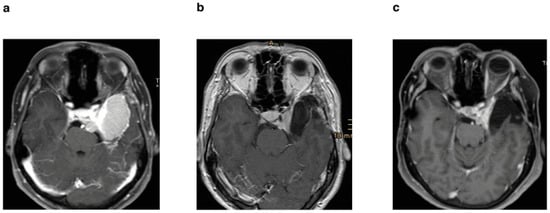

Figure 3. (a) Preoperative axial T1-weighted sequence with gadolinium enhancement of a patient who underwent STR without postoperative stereotactic radiotherapy; (b) postoperative MRI after 3 months; (c) follow-up MRI after 6 years with progression.

Secondly, patients were divided on the basis of tumor resection. We identified 58 (61%) patients with near-total resection and 37 (39%) patients with subtotal resection (Table 1) (Figure 2a). A tumor recurrence was observed after near-total resection in nine (9.4%) patients. In contrast, 18 patients (18.9%) showed progression after subtotal resection. Both in the Kaplan–Meier analysis (p = 0.0011) (Figure 2b) and in the univariate (p ≤ 0.0018) and multivariate analysis (p ≤ 0.0001), the groups differed significantly (Table 2) (Figure 3).

Our institution has a protocol to resect the tumors as safely as possible, with special attention paid to the improvement of neurological symptoms, where, e.g., a decompression of the optic nerve canal is performed to maximize visual acuity. With this in mind, a resection of the intracavernous portion of the tumors was never attempted (see Section 2). In line with this, our cohort was divided into NTR and STR groups. We observed that STR of MSWM with invasion of cavernous sinus was associated with worse PFS, when compared to NTR (Figure 2b, Table 2), which was achieved despite the risks associated with ICA tumor infiltration and involvement of further neighboring neurovascular structures. Although our study is not directly comparable to other studies in the literature, which classified the rate of GTR depending on the presence of CS invasion [4,5], included techniques for resection of the intracavernous portion of MSWMs [6], or demonstrated similar recurrence rates after GTR and STR [11], our results still highlight the importance of a better degree of resection to prolong PFS; however, this should be aimed at while maintaining functionality.